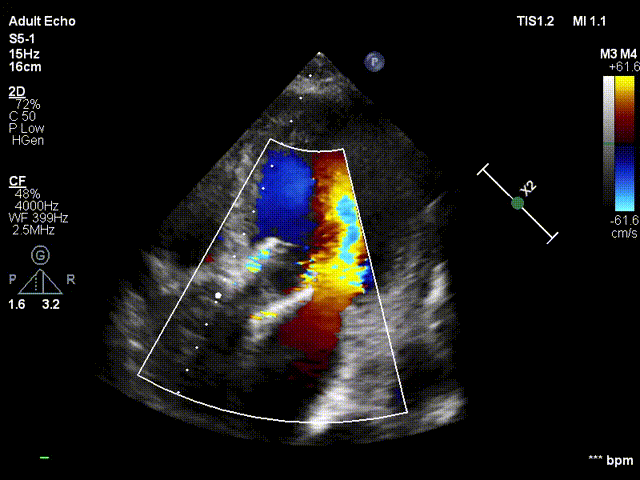

患者为83岁老年女性,主因“发作性胸闷胸痛10余年,加重1周”入院。患者病史明确,10余年来于多家医院诊断为“心功能不全”,予以保守治疗。1周前患者胸闷、胸痛加重,伴呼吸困难,活动后加重,夜间不能平卧。遂来我院就医,急诊心电图示“窦性心律”;胸部CT示“双肺散在炎症灶、心脏增大、肺动脉干增粗、双侧少量胸腔积液”;超声示“升主动脉硬化、主动脉瓣狭窄(重度)、主动脉瓣反流(中度)、二尖瓣反流(中度)。左室舒张末内径62mm、左房内径41mm、室间隔厚度9mm、主动脉瓣峰值压差56mmHg、LVEF 51%”。